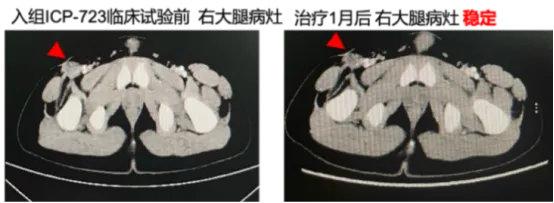

注册研究显示,佐来曲替尼在NTRK融合阳性实体瘤中展现出卓越疗效[7]:总缓解率(ORR)达89.1%,而其中青少年患者的ORR更是达到了100%;疾病控制率(DCR)96.4%,表明几乎所有患者病情均得到有效控制;24个月无进展生存率(PFS)77.4%,总生存率(OS)90.8%,证实了该药能帮助绝大多数患者实现长期缓解。